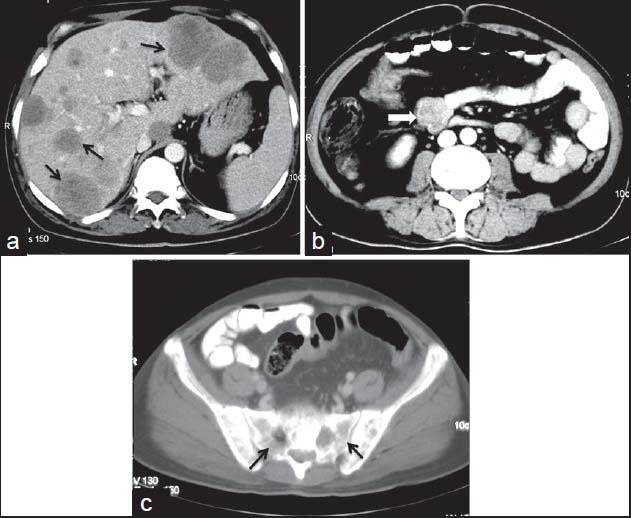

| Figure 15:Malignant small bowel gastrointestinal stromal tumors in 45-year-old male — (a) contrast-enhanced computed tomography (CECT) showing multiple liver metastases (arrows) (b) axial CECT image showing heterogenous mass lesion with exophytic component (arrowhead) arising from jejunal loop (c) CECT bone window showing bony metastases (arrows)

| Figure 15:Malignant small bowel gastrointestinal stromal tumors in 45-year-old male — (a) contrast-enhanced computed tomography (CECT) showing multiple liver metastases (arrows) (b) axial CECT image showing heterogenous mass lesion with exophytic component (arrowhead) arising from jejunal loop (c) CECT bone window showing bony metastases (arrows)

On imaging, GISTs may be submucosal, intramural or subserosal. Findings on barium studies are often subtle than seen on computed tomography (CT) as majority of them are exophytic in nature. On CT, small GISTs are usually well-defined, solid mass showing homogenous enhancement [Figure 9]. Calcifications may occasionally be present. Large tumors show areas of hemorrhage, cystic/necrotic areas and heterogeneous enhancement. Neovascularity may be seen within the tumor after contrast administration [Figure 10]. Thrombosis of mesenteric vessels is uncommon. Rarely, these tumors may be entirely cystic [Figure 11]. Cavitory nature with air and contrast within the mass is suggestive of mucosal ulceration with fistulous communication of necrotic cavity with the bowel lumen [Figure 12].[3,4] Collection of air in the nondependent aspect of larger cavitating tumors with necrosis is known as the “Toricelli-Bernouilli” crescentic necrosis sign [Figure 13].[5] Uncommon features with GIST are presence of ascites, lymphadenopathy, intestinal obstruction and metastases in lungs [Figure 14]. Crucial role lies in differentiation of benign versus malignant GISTs. Features associated with poor prognosis include distal location, size and high mitotic activity with the exception of esophageal GISTs.[6] Benign lesions are usually <2>5 cm.[7] Smaller tumors should be classified as at lower risk for malignancy rather than as benign. Tumor necrosis, cystic change, nuclear atypia, tumor vascularity, and degree of staining for CD117 are unreliable predictors of malignancy.[8] Metastases are most common in the liver, mesentery, and peritoneum [Figure 15].[9,10] Calcification is usually seen in metastases after specific chemotherapy.